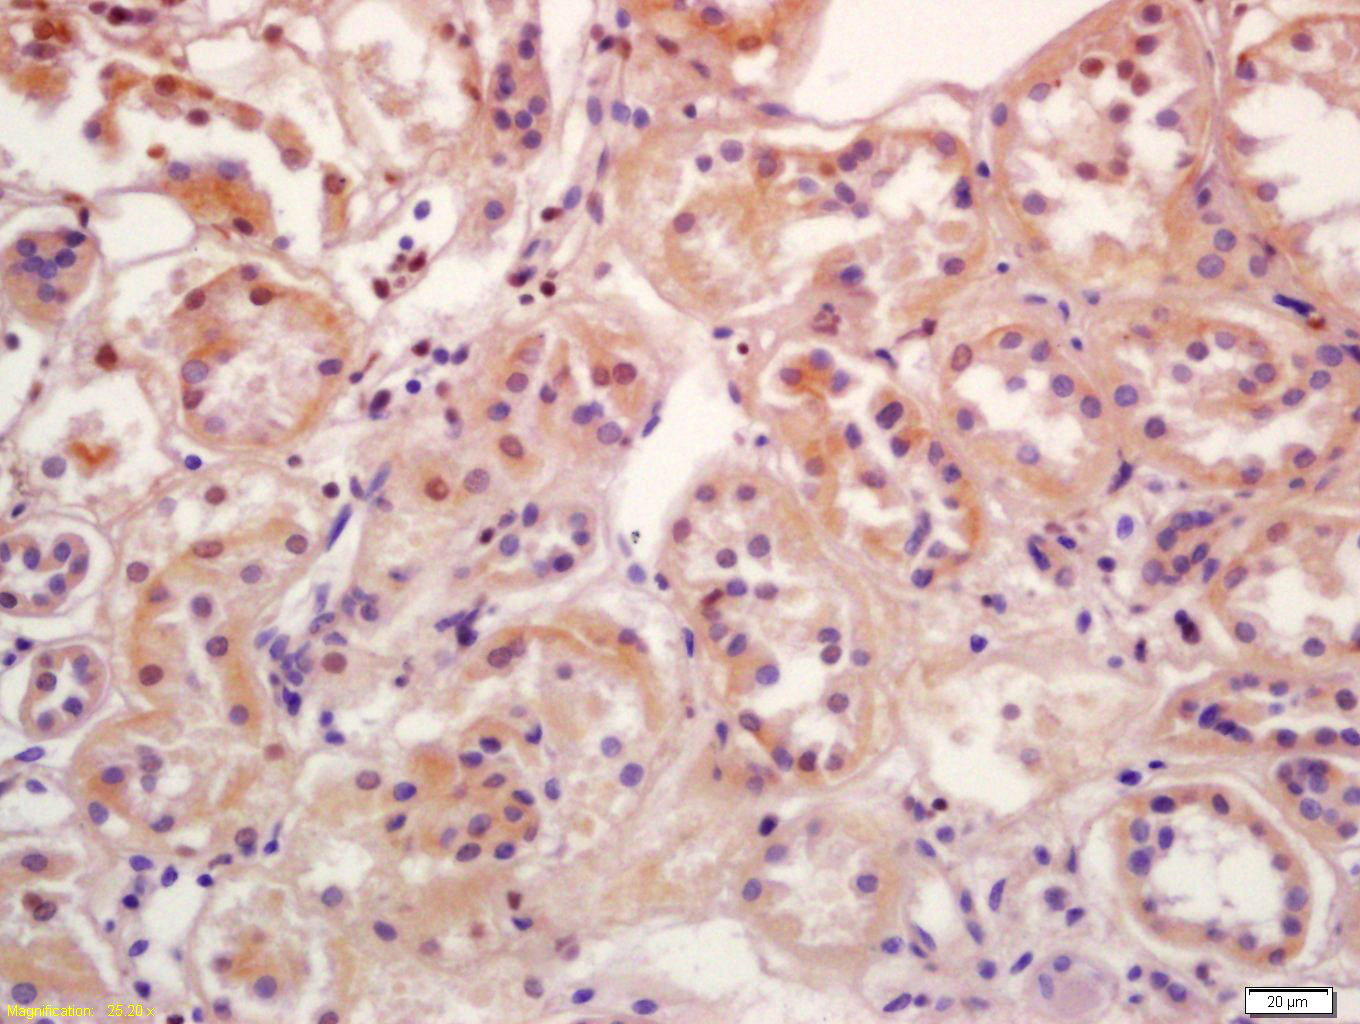

| IHC-P | Human, Mouse, Rat | Pig, Cow, Dog, Horse | 1:100-500 |